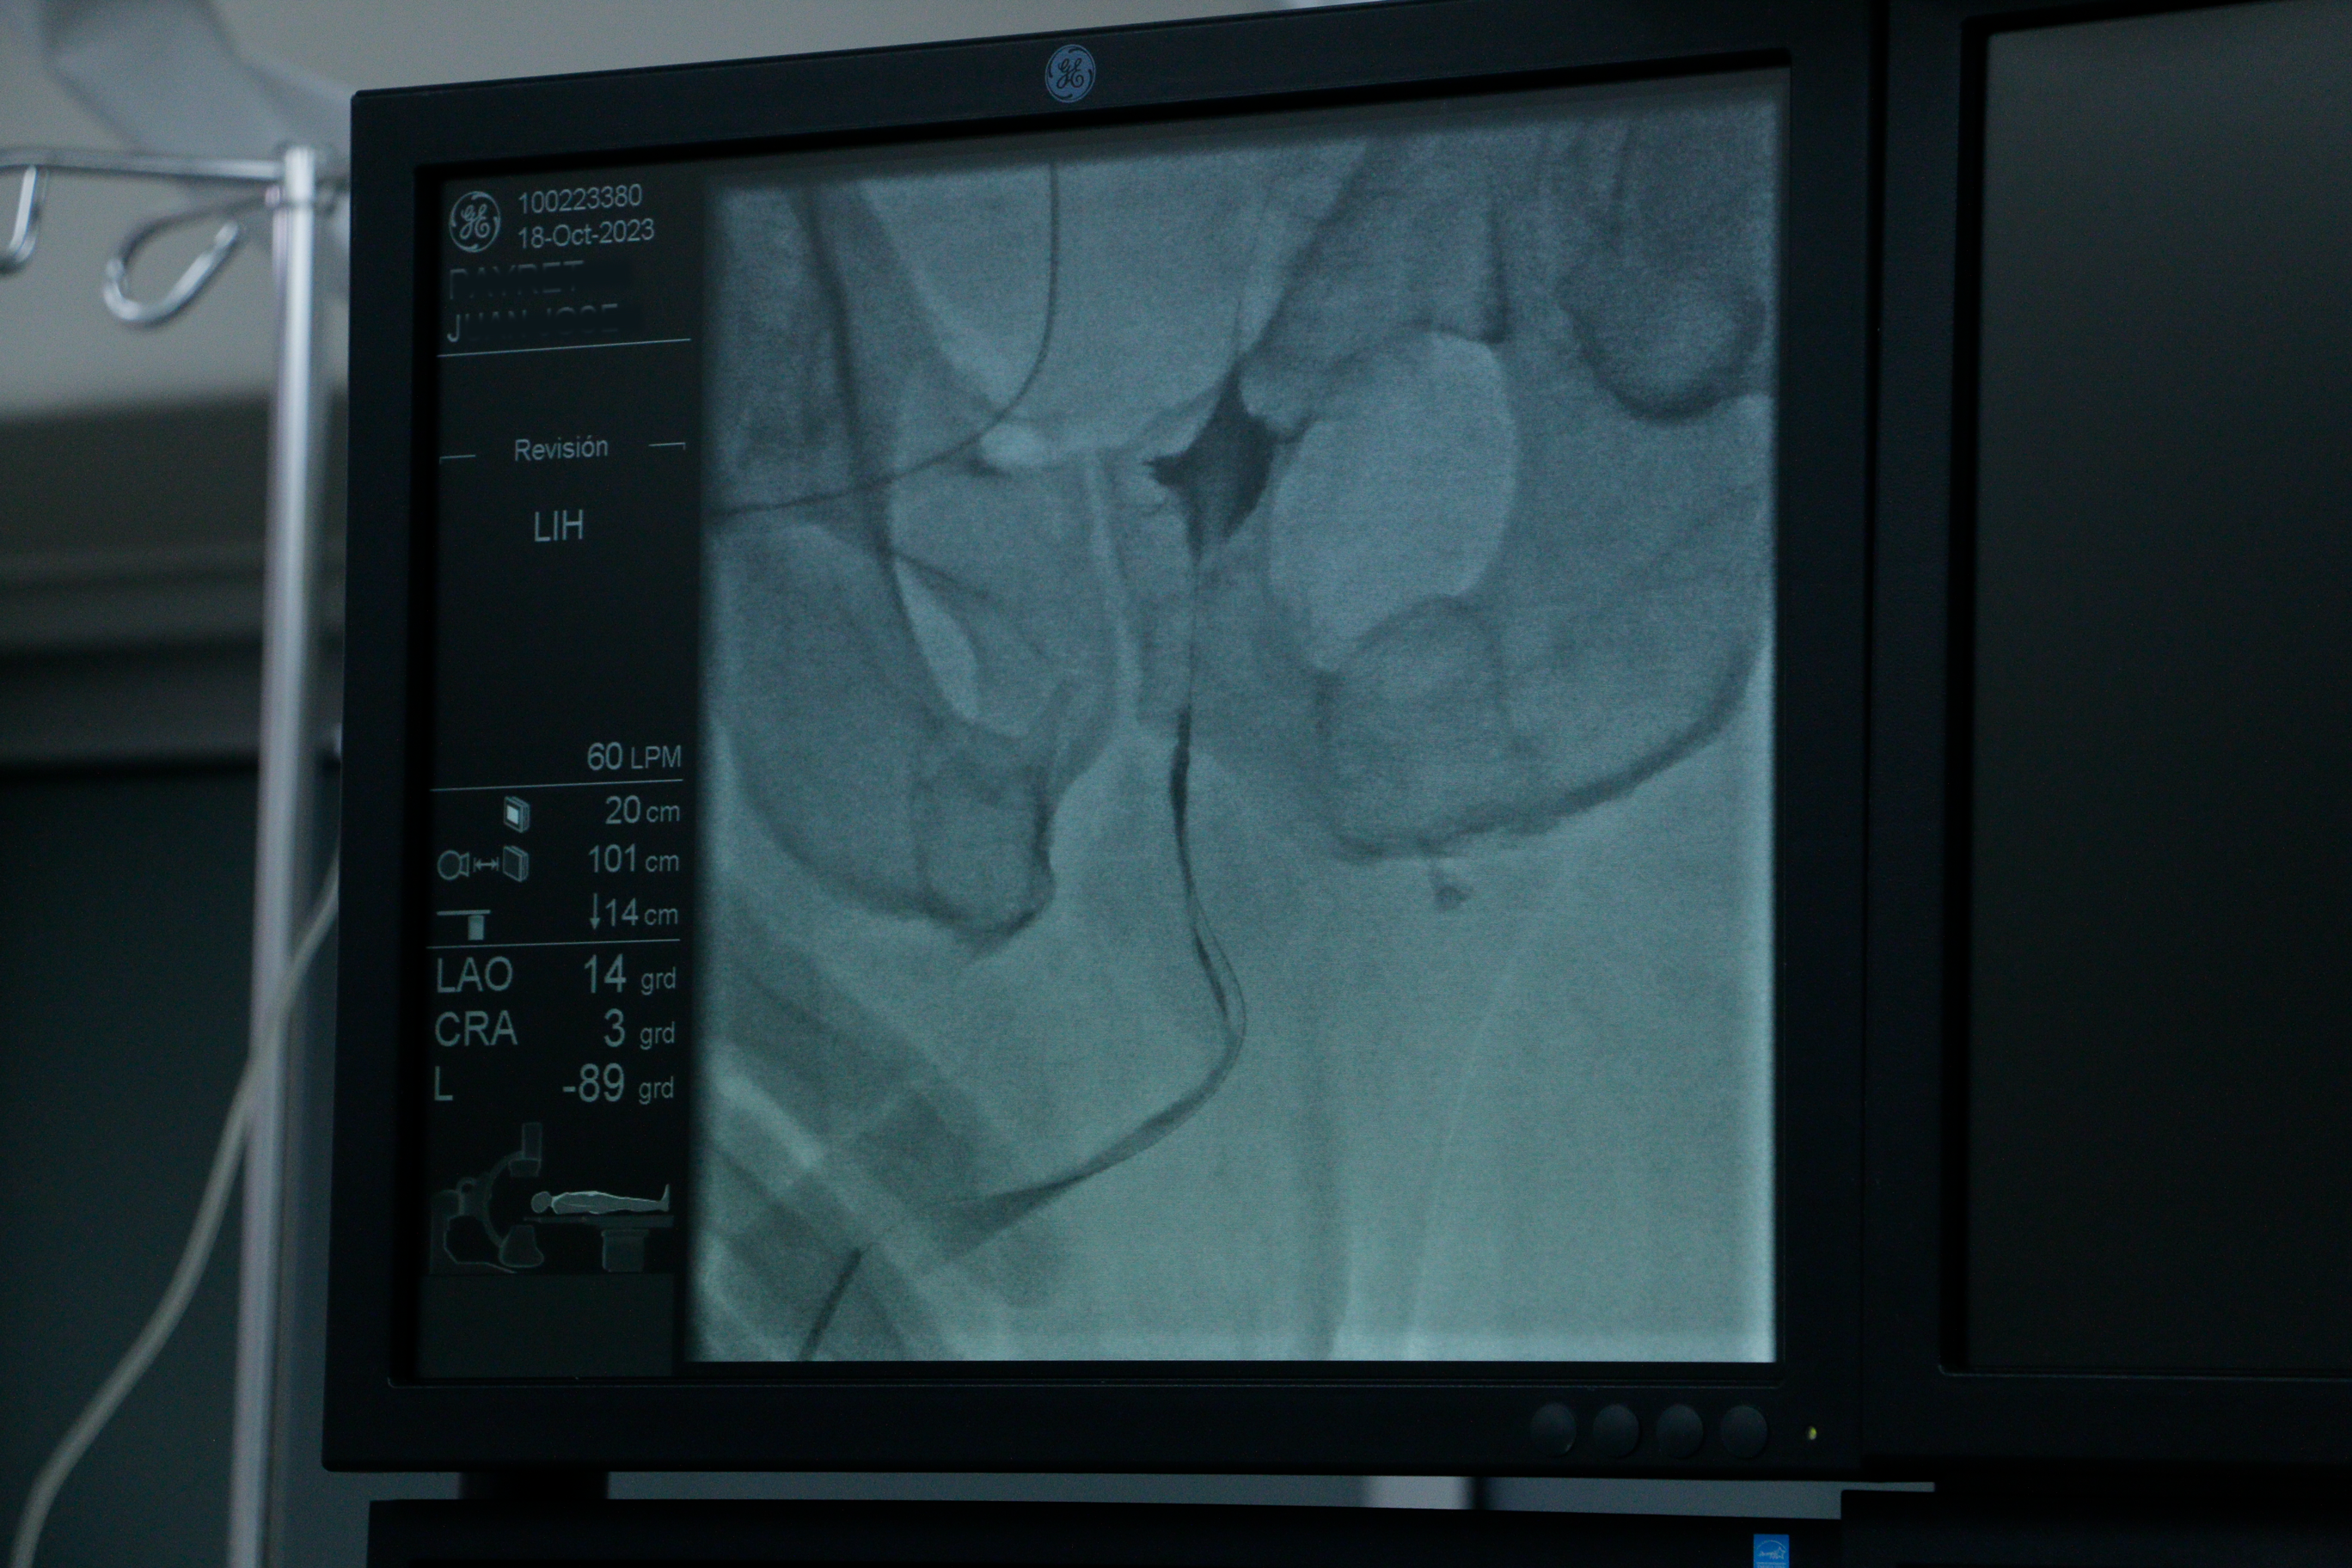

Uretroplastía procedimiento combinado mini Uretrotomía interna cutting balloon balón con paclitaxel